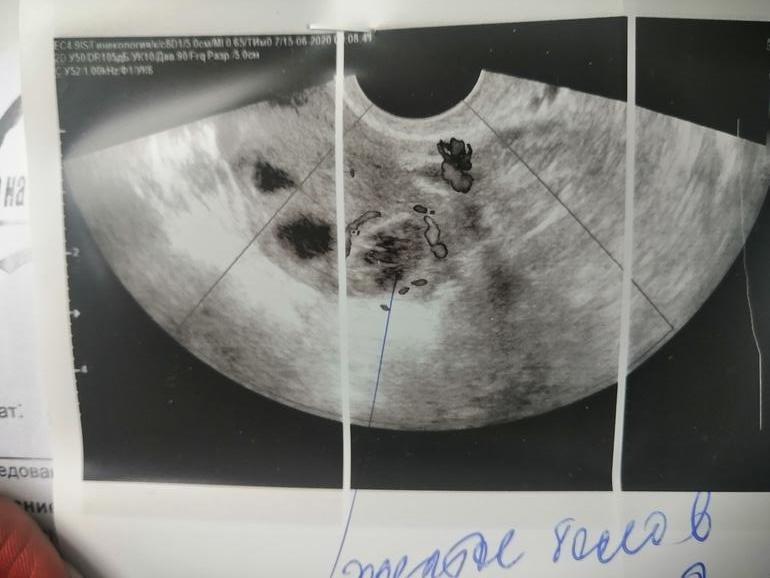

Ktoria в Зачатие 5 лет Так выглядит жт? Фолликулометрия Много кто просил сфотать, когда пойду на узи. Посмотрите еще 20 записей на эту тему Отменить Ответить Карина у меня такое жт, может кому пригодится тоже 🙈 22.06.2020 Ответить Девочки, подскажите ! Тонкий эндометрий Чаты Беременных Выберите чат: Январята-2026 Февралята-2026 Мартята-2026 Апрелята-2026 Майчата-2026 Июнята-2026 Июлята-2026 Августята-2026